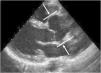

The main cardiovascular manifestation of MFS is dilatation of the aortic root and the proximal ascending aorta, with effacement of the sinotubular junction. This is found in 80% of MFS patients and can lead to aortic dissection, which is the leading cause of premature death in these patients (Figures 5 and 6).3,12,41,49–51 The ascending aorta is most severely affected due to its higher elastic fiber content and to its exposure to repeated hemodynamic stress from left ventricular ejection.2,50,52,53

Cardiovascular study usually entails transthoracic echocardiography to determine the maximum diameter of the aortic root at the sinus of Valsalva in at least three transthoracic images. The mean diameter should be corrected for age and body surface area (BSA) and interpreted according to the Z-score; Roman et al. created a nomogram for aortic root diameter in relation to BSA and age.6,70,71 If transthoracic echocardiography does not allow precise visualization of the proximal aorta, transesophageal echocardiography, computed tomography or magnetic resonance imaging should be performed, using the same nomogram to obtain correct diameter measurements.6 The latter imaging modalities are also indicated for study of the distal aorta. Echocardiography is also valuable for assessment of morphological and functional alterations of the mitral and tricuspid valves.